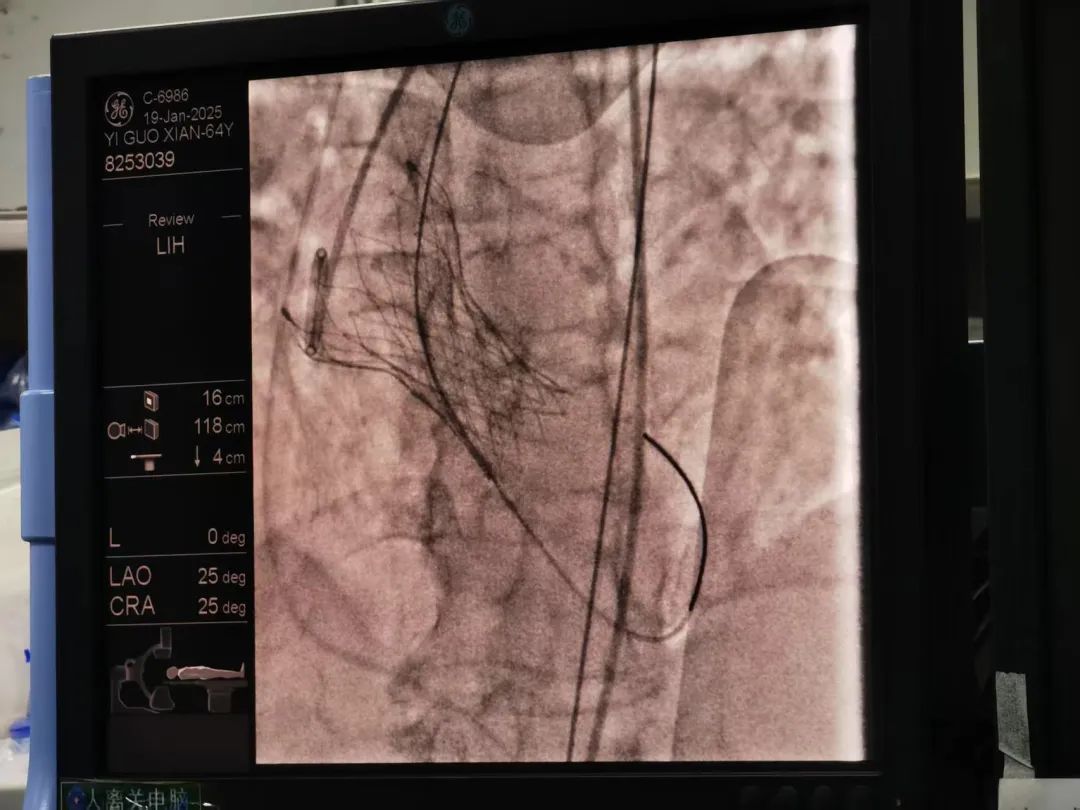

患者术后影像

医院麻醉医师周菲帮患者顺利进行了全身麻醉,心血管内科一区主任戴斌、二区主任王苏燕与湘雅附二心血管内科方臻飞、唐建军教授同台协作,沿右颈静脉入路置入临时起搏器,将其置入右室心尖位置,连接起搏器备用。术中成功进行股动脉穿刺,并行升主动脉造影显示左右冠脉管血流情况、主动脉返流情况等,术前测患者左室及主动脉收缩压压差高达117mmHg,术中球囊顺利通过主动脉瓣狭窄处,成功行主动脉瓣球囊扩张一次,送经导管主动脉心脏瓣膜TarusEIite-AV26mm生物瓣成功通过主动脉狭窄处,精确定位后释放生物瓣,经导管主动脉瓣置换顺利完成,术后再行主动脉根部测压跨瓣压差恢复正常为0!复查经胸心脏彩超及心脏血管造影,各处血流均恢复正常,保留左侧股动脉鞘及临时起搏器,经过两个多小时的精心操作,手术非常成功,此时此刻,大家终于松了一口气。